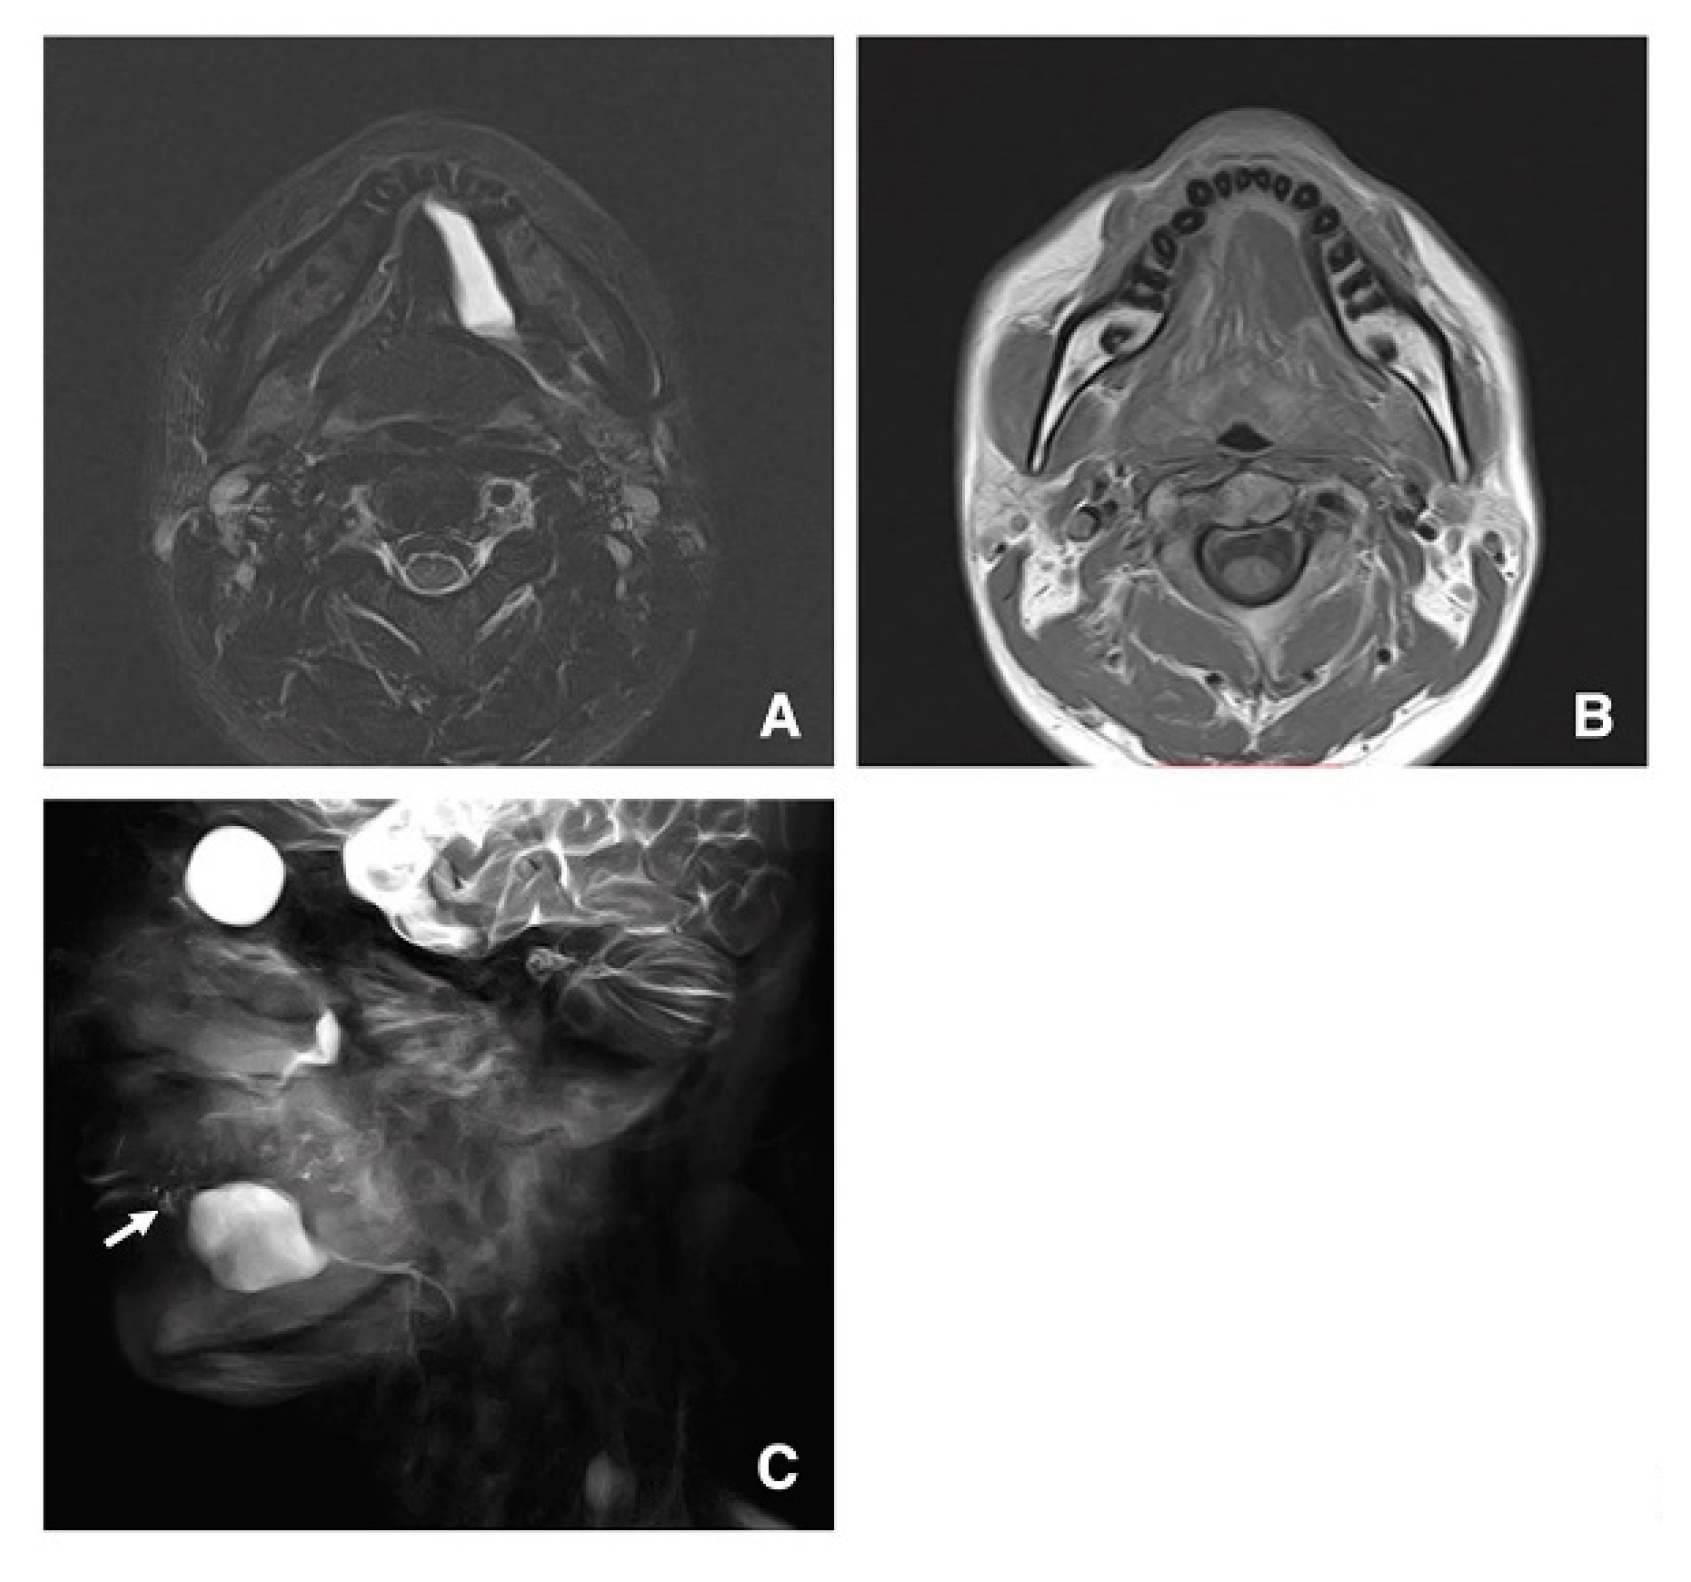

3.3. Clinical Application of MR Sialography for Patients with Sublingual Gland Diseases